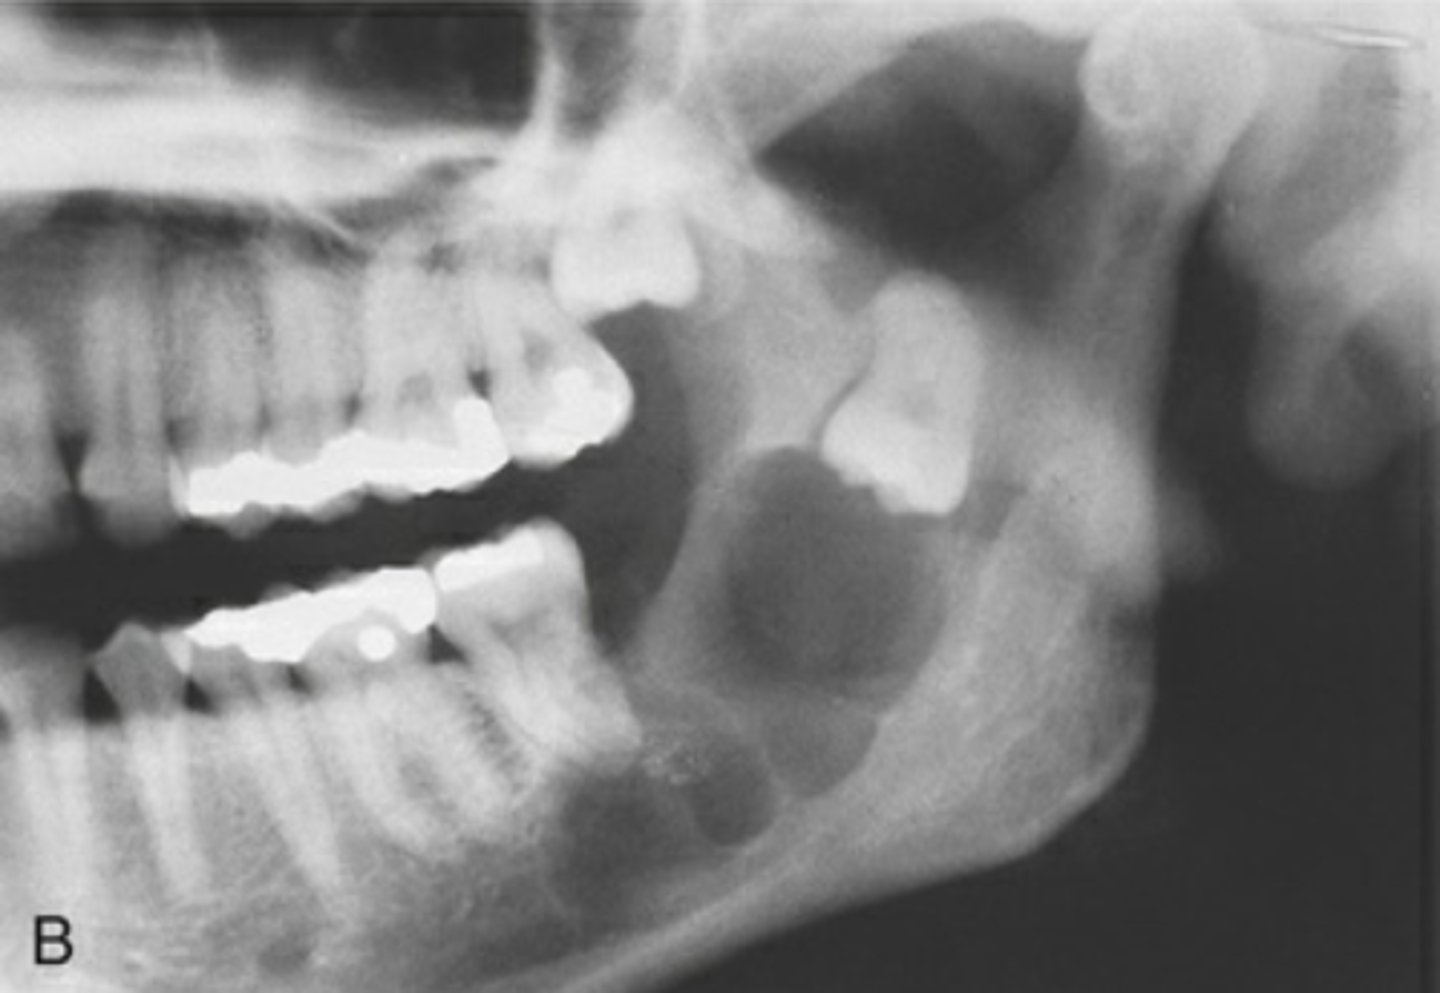

What are the radiographic features of ameloblastomas?

⢠unilocular radiolucency (early lesions)

⢠multilocular radiolucency (honeycomb/soap bubble) (large lesions)

⢠cortical thinning/bone expansion

⢠resorption of adjacent tooth roots + tooth displacement